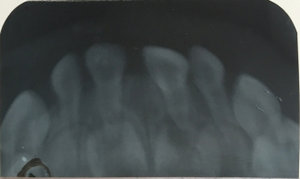

Что делать, если ребенок ударился об стол передним зубом, и он вывернулся во внутрь?